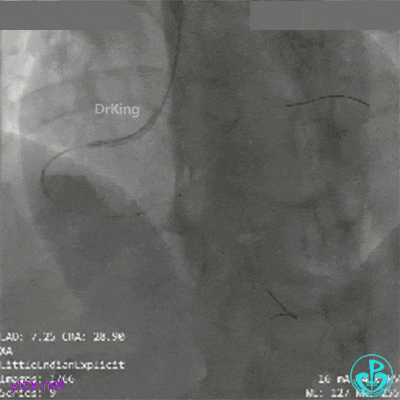

球囊再次扩张远端后,替罗非班注射,示远端狭窄改善,近端出现什么情况?血栓?夹层?

直接指引导管抽吸,未见血栓。

冒烟显示近端仍然有异物,远端造影剂滞留。

高度怀疑近端夹层。